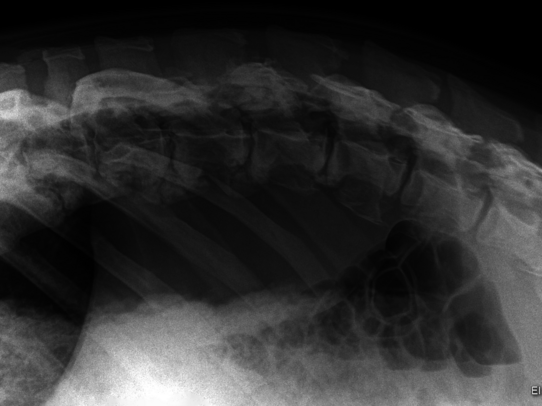

Case 2: Babirusa

The male deer Kendari (born in 2009) first showed signs of abnormality in the summer of 2024: reduced food intake and a curved posture. Due to his trustfulness, he could be X-rayed in a standing position without sedation. The digital images showed pronounced spondylarthrosis along the spine.

Despite targeted pain therapy, his condition deteriorated within a few days, so that after intensive consultation, euthanasia was performed. The subsequent autopsy revealed that, in addition to the arthrosis, there was a far-advanced spindle cell sarcoma with numerous metastases in the body, although the fallow deer had shown no previous symptoms in this regard.